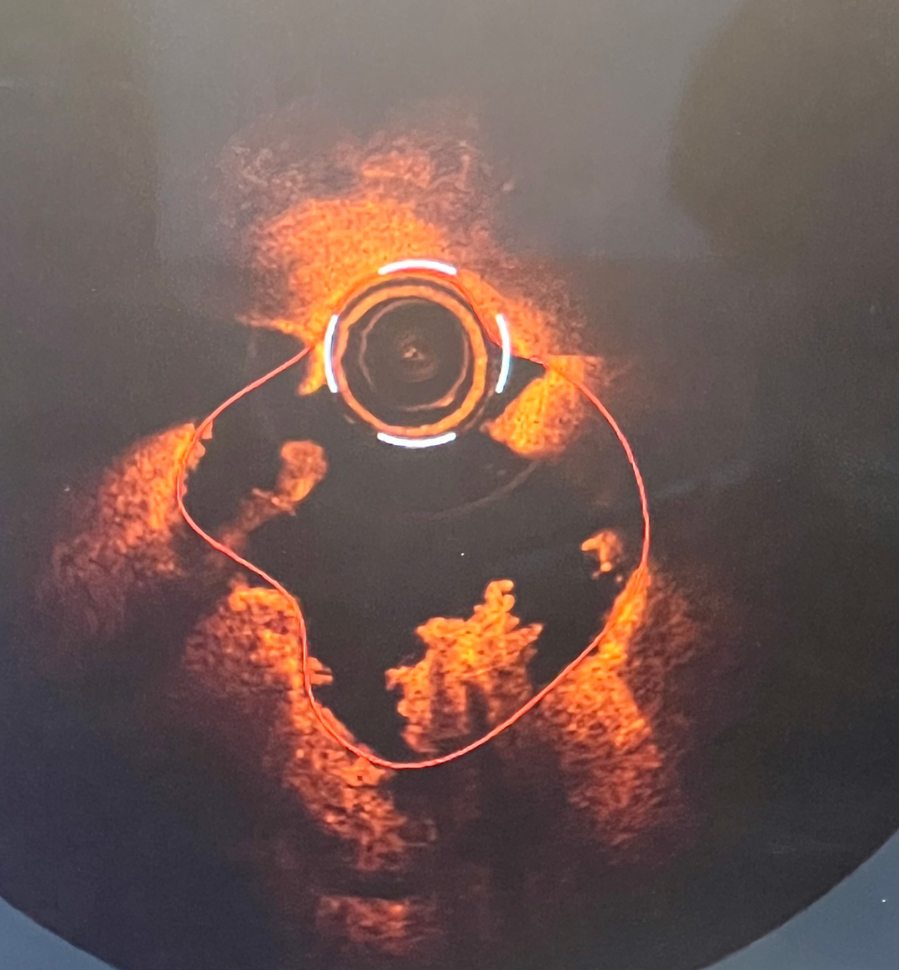

What's the "Cauliflower" on OCT?

A 65-year-old gentleman with a medical history of diabetes mellitus and hypertension presented with NSTEMI.

- Underwent coronary angiography in the cath lab

- Optical coherence tomography was performed for lesion assessment

- OCT intrigued physicians about the vulnerability and prompted immediate management

Thrombosis seen in artery